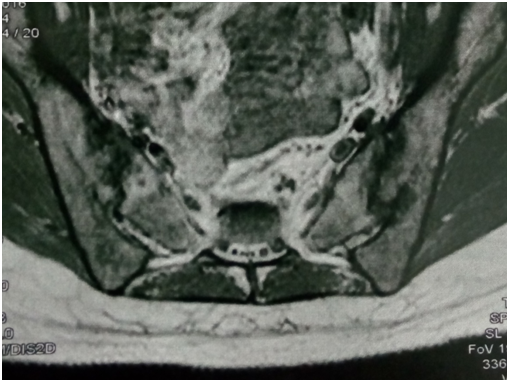

Radiological changes in the form of SIJ destruction/sclerosis (x-ray, CT) were evident in 10 of the 13 patients. MRI evidence of SIJ infection was noted on STIR sequence images in all 13 patients. The pathogens isolated were Staph. aureus in 69% (9 patients), streptococci in 23% (3 patients), and E.coli in 7% (1 patient).

MRI represents the most sensitive and specific method in early diagnosis of infectious sacroiliitis. The short tau inversion recovery sequence (STIR) was found to be more effective than the T1 contrast-enhanced sequence, particularly in delineating all findings of the SI joint inflammation and allowing for the early detection of septic sacroiliitis.2

Figure 1 widening of left SIJ space on coronal fat suppression T2 with high signal intensity denoting pus more on the left side joint.